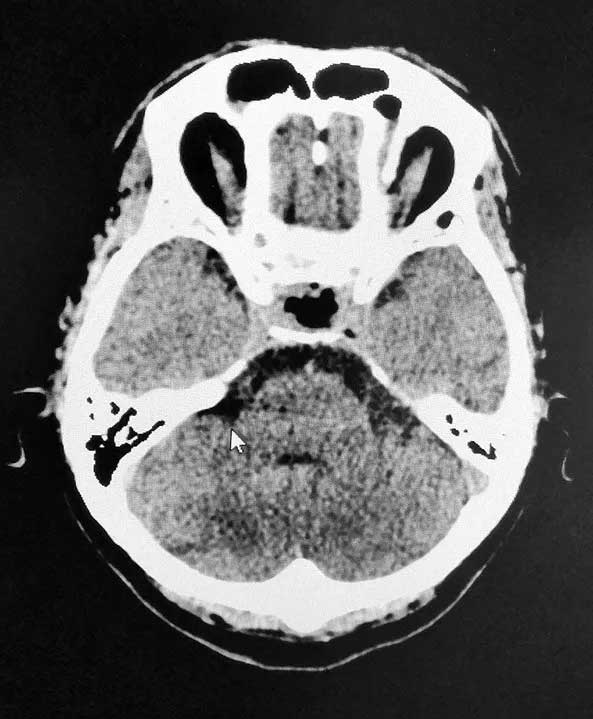

近期,上海蓝十字脑科医院6B病区收治了这样一位典型患者。一位男性垂体瘤患者,患者一年前出现视物模糊情况,起初他以为是眼睛问题,但是到医院眼科检查时未查出明显异常。来院后经检查,患者双侧视野缺损,后经医院MR检查确诊为3公分垂体巨大腺瘤。患者手术指征明确,无明显手术禁忌,在征得家属同意后,李士其教授在吴治群博士协助下经蝶窦入路成功为患者进行了手术,显微镜下将鞍内肿物切除。经过十余天恢复,目前患者已顺利出院。

▲ 术后影像,肿瘤被切除